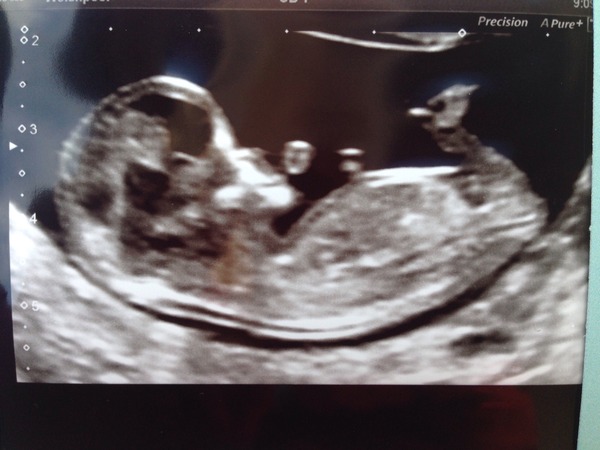

I had my 12 week scan this morning. I have a real baby looking baby now. No longer a pizza slice. Dates only out by 1 day so I'm now 12+2. The big tell the family marathon is in progress and we're telling the bulk of peopl tonight via the medium of Facebook.

Everything all fine Shelb thanks. They showed us everything which was amazing and baby was moving around so much. DH commented on "it looks like it's in a washing machine". Did the NT measurement and had my bloods taking for the combined screening and I'm all Booked in for my 16 week appointment and 19 week abnormality scan. £5 for scan a photo! Glad I'd read that some places charge.

Very excited. DH has adopted the hilarious approach of texting his friends with the scan photo saying "Boom sex trophy"!!

Congrats Bunch that is a lovely clear image! Bet your pleased everything is on track. Fx for you that everything comes back good from the tests. I love how men take the credit for their superior sperm whilst you're the one puffing and panting and building a baby!Wink